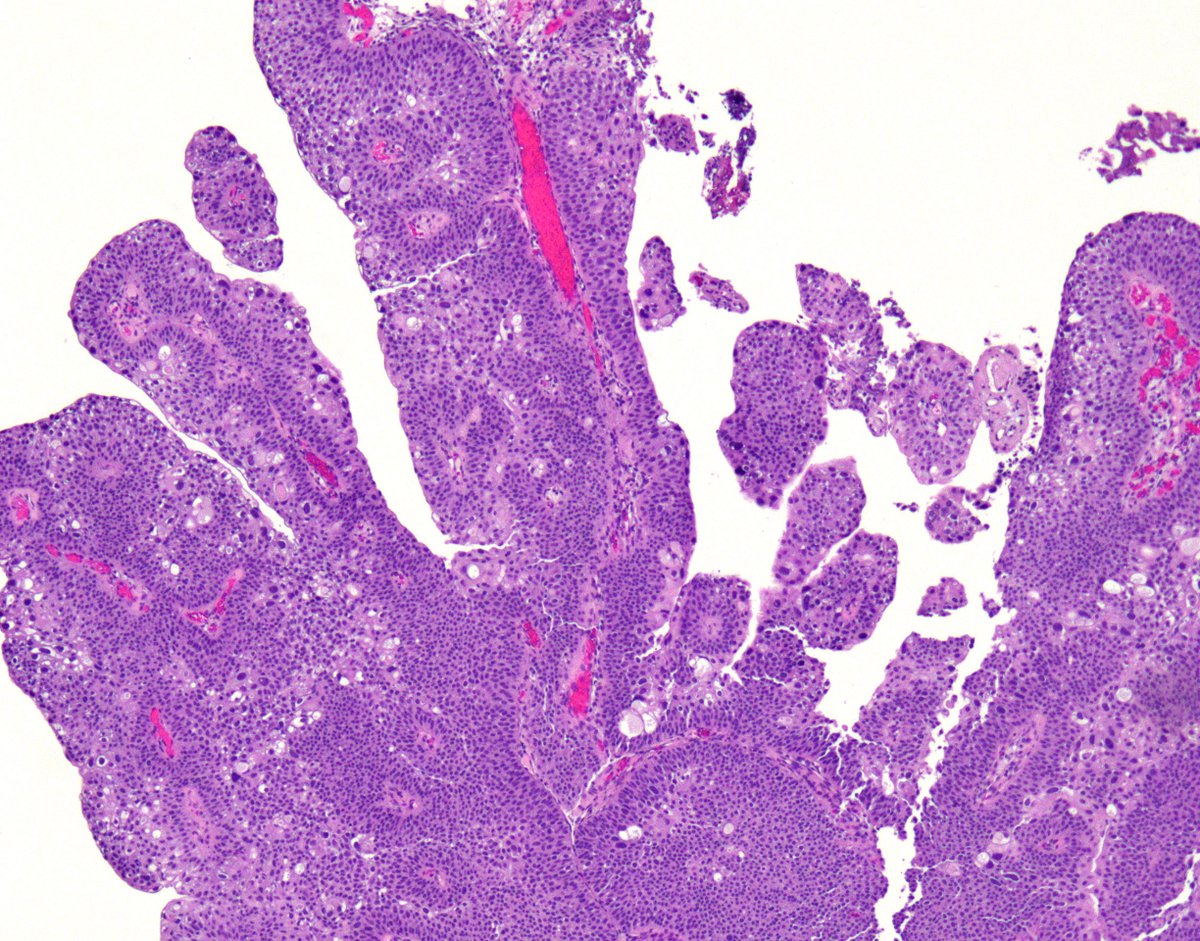

🚨Diagnostic Pitfall Alert!! When encountering extreme umbrella cell atypia, fusion of papillae within a tumor can convey a higher grade appearance #gupath😱 beware!